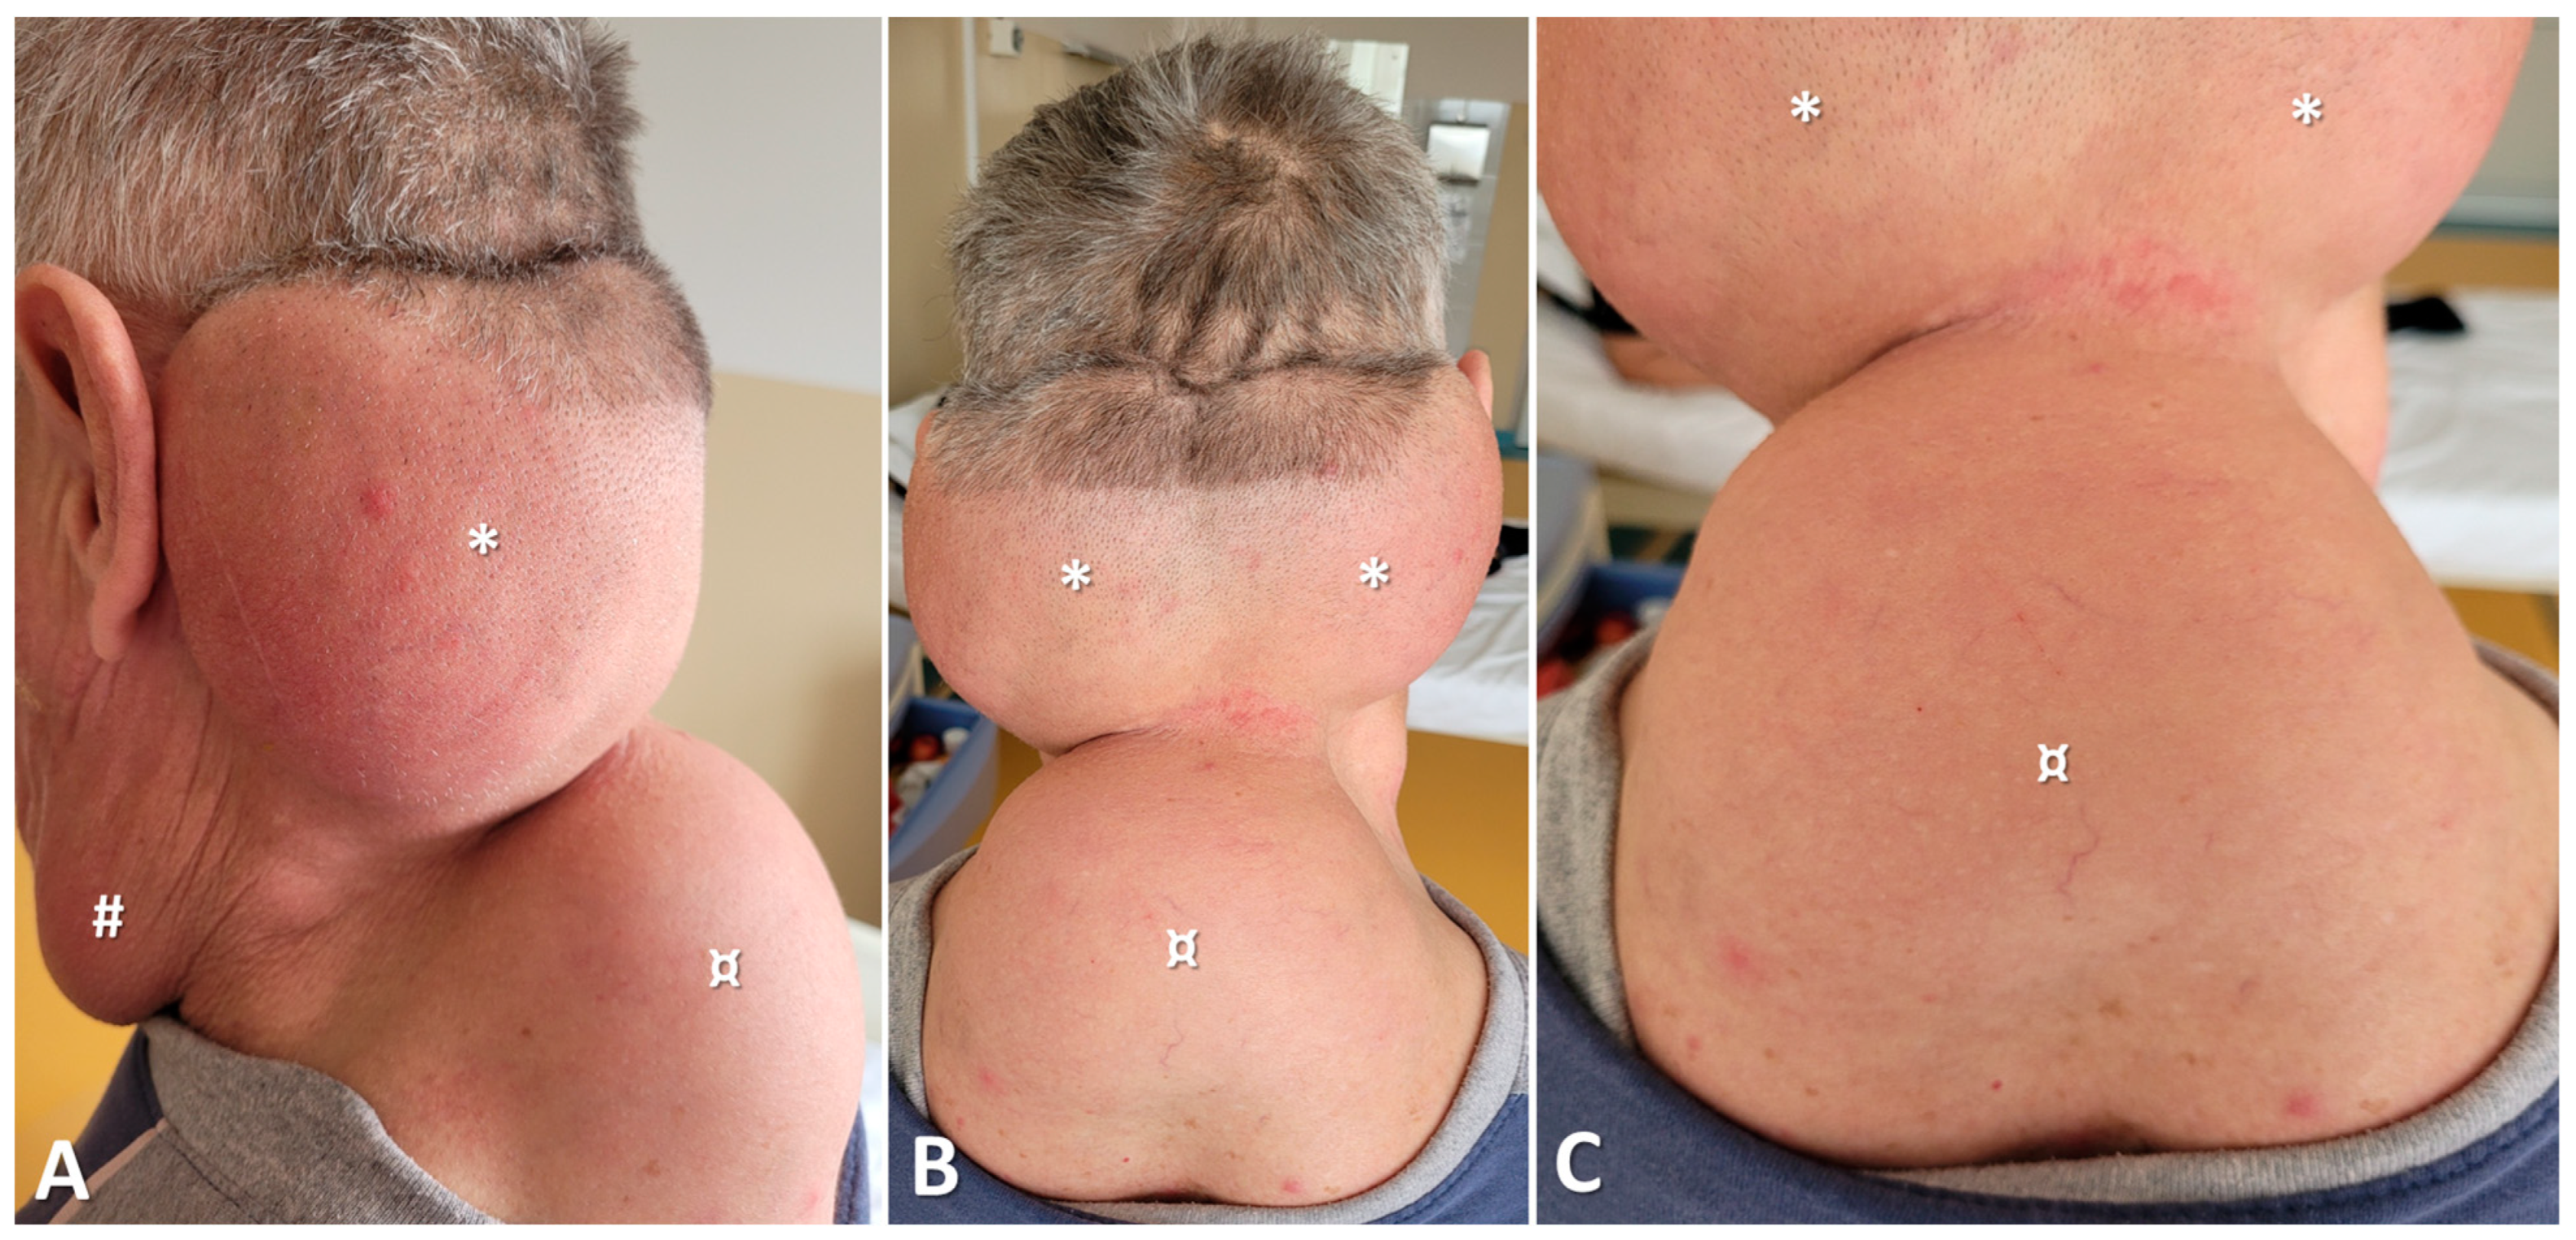

2.1. Clinical Data

3.3. Clinical Presentation